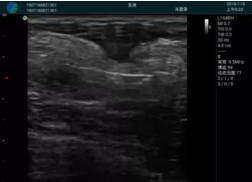

可視化穿刺引導(dǎo)

M20實(shí)時引導(dǎo):向包塊后方間隙注射利多卡因

清晰顯示腺體內(nèi)低回聲快影,邊界清晰,包膜較光滑

確定進(jìn)針路徑并實(shí)時監(jiān)測抽吸針與腫塊位置關(guān)系